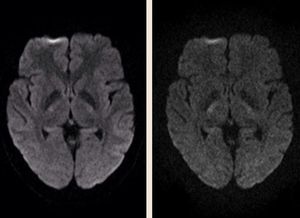

b-value is a parameter that reflects the strength and timing of the gradients used to generate diffusion-weighted images. The higher the b-value, the stronger the diffusion effects. The "optimal" choice of b-value is not clearly defined and depends upon field strength, available RF coils and gradients, number of signals averaged, anatomical features and predicted pathology. Two brain images using b-values of 1000 (left) and 2000 (right) s/mm² below show progressively more diffusion weighting (as evidenced by the brighter corticospinal tracts) but also less SNR.